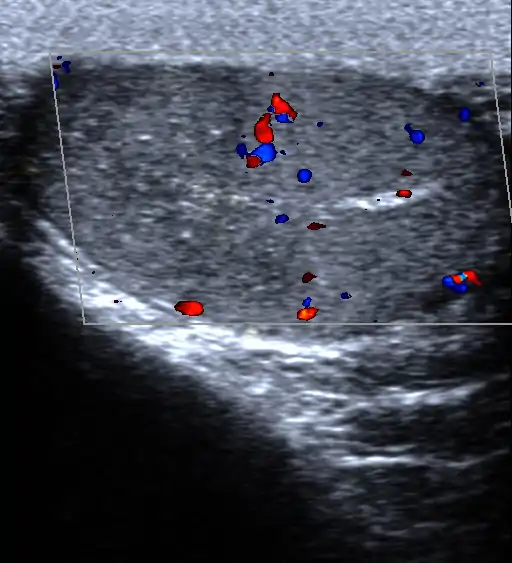

درد بیضه

درد بیضه ممکن است در هر دو بیضه یا یکی از آنها احساس شود و بسته به دوره زمانی، میتواند شدید، نیمهشدید یا مزمن باشد.

درد بیضه آن است که قسمتی یا تمام یک یا هر دو بیضه آسیب ببیند یا درد بگیرد.